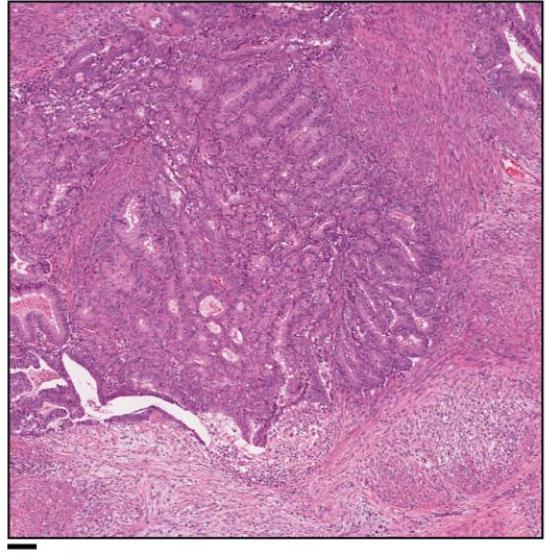

The introduction of this research paper highlights the transformative advancements in computational pathology, driven by the integration of digital slide scanning, artificial intelligence (AI), large datasets, and high-performance computing resources. Researchers have successfully applied deep learning techniques to various tasks such as cancer subtyping, grading, metastasis detection, and treatment response prediction. Despite these advancements, the role of natural language in pathology remains underutilized, which could enhance model development and facilitate user interaction with AI systems.

The paper emphasizes the potential of multimodal large language models (MLLMs) and generative AI to revolutionize computational pathology by incorporating natural language processing. While existing models have shown promise in diagnostic tasks, they currently lack the capability to serve as interactive companions for pathologists. The authors propose that an AI copilot could significantly aid clinical decision-making, education, and research by providing initial assessments of histopathology images, suggesting differential diagnoses, and summarizing morphological features of large datasets. This innovative approach could democratize access to expert guidance in pathology, addressing disparities in healthcare provision.

In this section, the authors discuss the development and evaluation of PathChat, a multimodal generative AI copilot designed for human pathology. PathChat integrates a custom, fine-tuned multimodal large language model (MLLM) that combines a vision encoder pretrained on extensive histology image data with a 13 billion parameter Llama 2 language model. This architecture allows PathChat to process and respond to complex pathology-related queries by leveraging both visual and textual inputs. The model was evaluated against state-of-the-art competitors, including LLaVA and GPT-4Vision, demonstrating superior diagnostic accuracy and response quality in both multiple-choice and open-ended question formats.

The evaluation results indicate that PathChat significantly outperforms the other models, achieving an accuracy of 78.1% in image-only settings and 89.5% when additional clinical context is provided. In open-ended question answering, PathChat scored an overall accuracy of 78.7%, surpassing GPT-4Vision by 26.4%. The authors highlight that PathChat excels particularly in tasks requiring detailed morphological analysis of histology images, while it performs comparably to GPT-4Vision in clinical knowledge retrieval tasks. The findings suggest that PathChat has the potential to enhance pathology education, research, and clinical decision-making, particularly in complex diagnostic scenarios. Future improvements may focus on refining the model’s ability to handle diverse input formats and ensuring accurate identification of invalid queries.